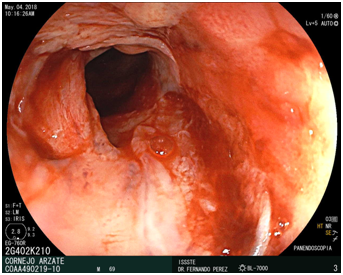

An UGE was performed, with PENTAX Pediatric video endoscope, a stricture of 80% of the lumen was visualized at proximal third esophagus, the length of 1cm, with no pass through of the scope. The final diagnosis was a Complex proximal third esophageal peptic stricture.

The role of surgery in benign stricture is largely limited to ant reflux procedures to manage the GERD that is etiologic in most benign strictures (Figure 1-5).

Figure 1 proximal third esophageal peptic stricture endoscopic view.

Figure 2 Proximal third esophageal peptic stricture endoscopic view.